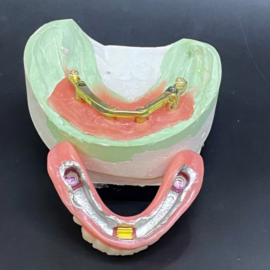

The process of implant dentures begins with a thorough dental examination and consultation with a dental implant specialist. During this visit, different options are discussed, and a personalized treatment plan is created based on your needs and medical history.

Receiving implant dentures is a multi-step process that includes placing the dental implants and securely attaching the dentures with precision.